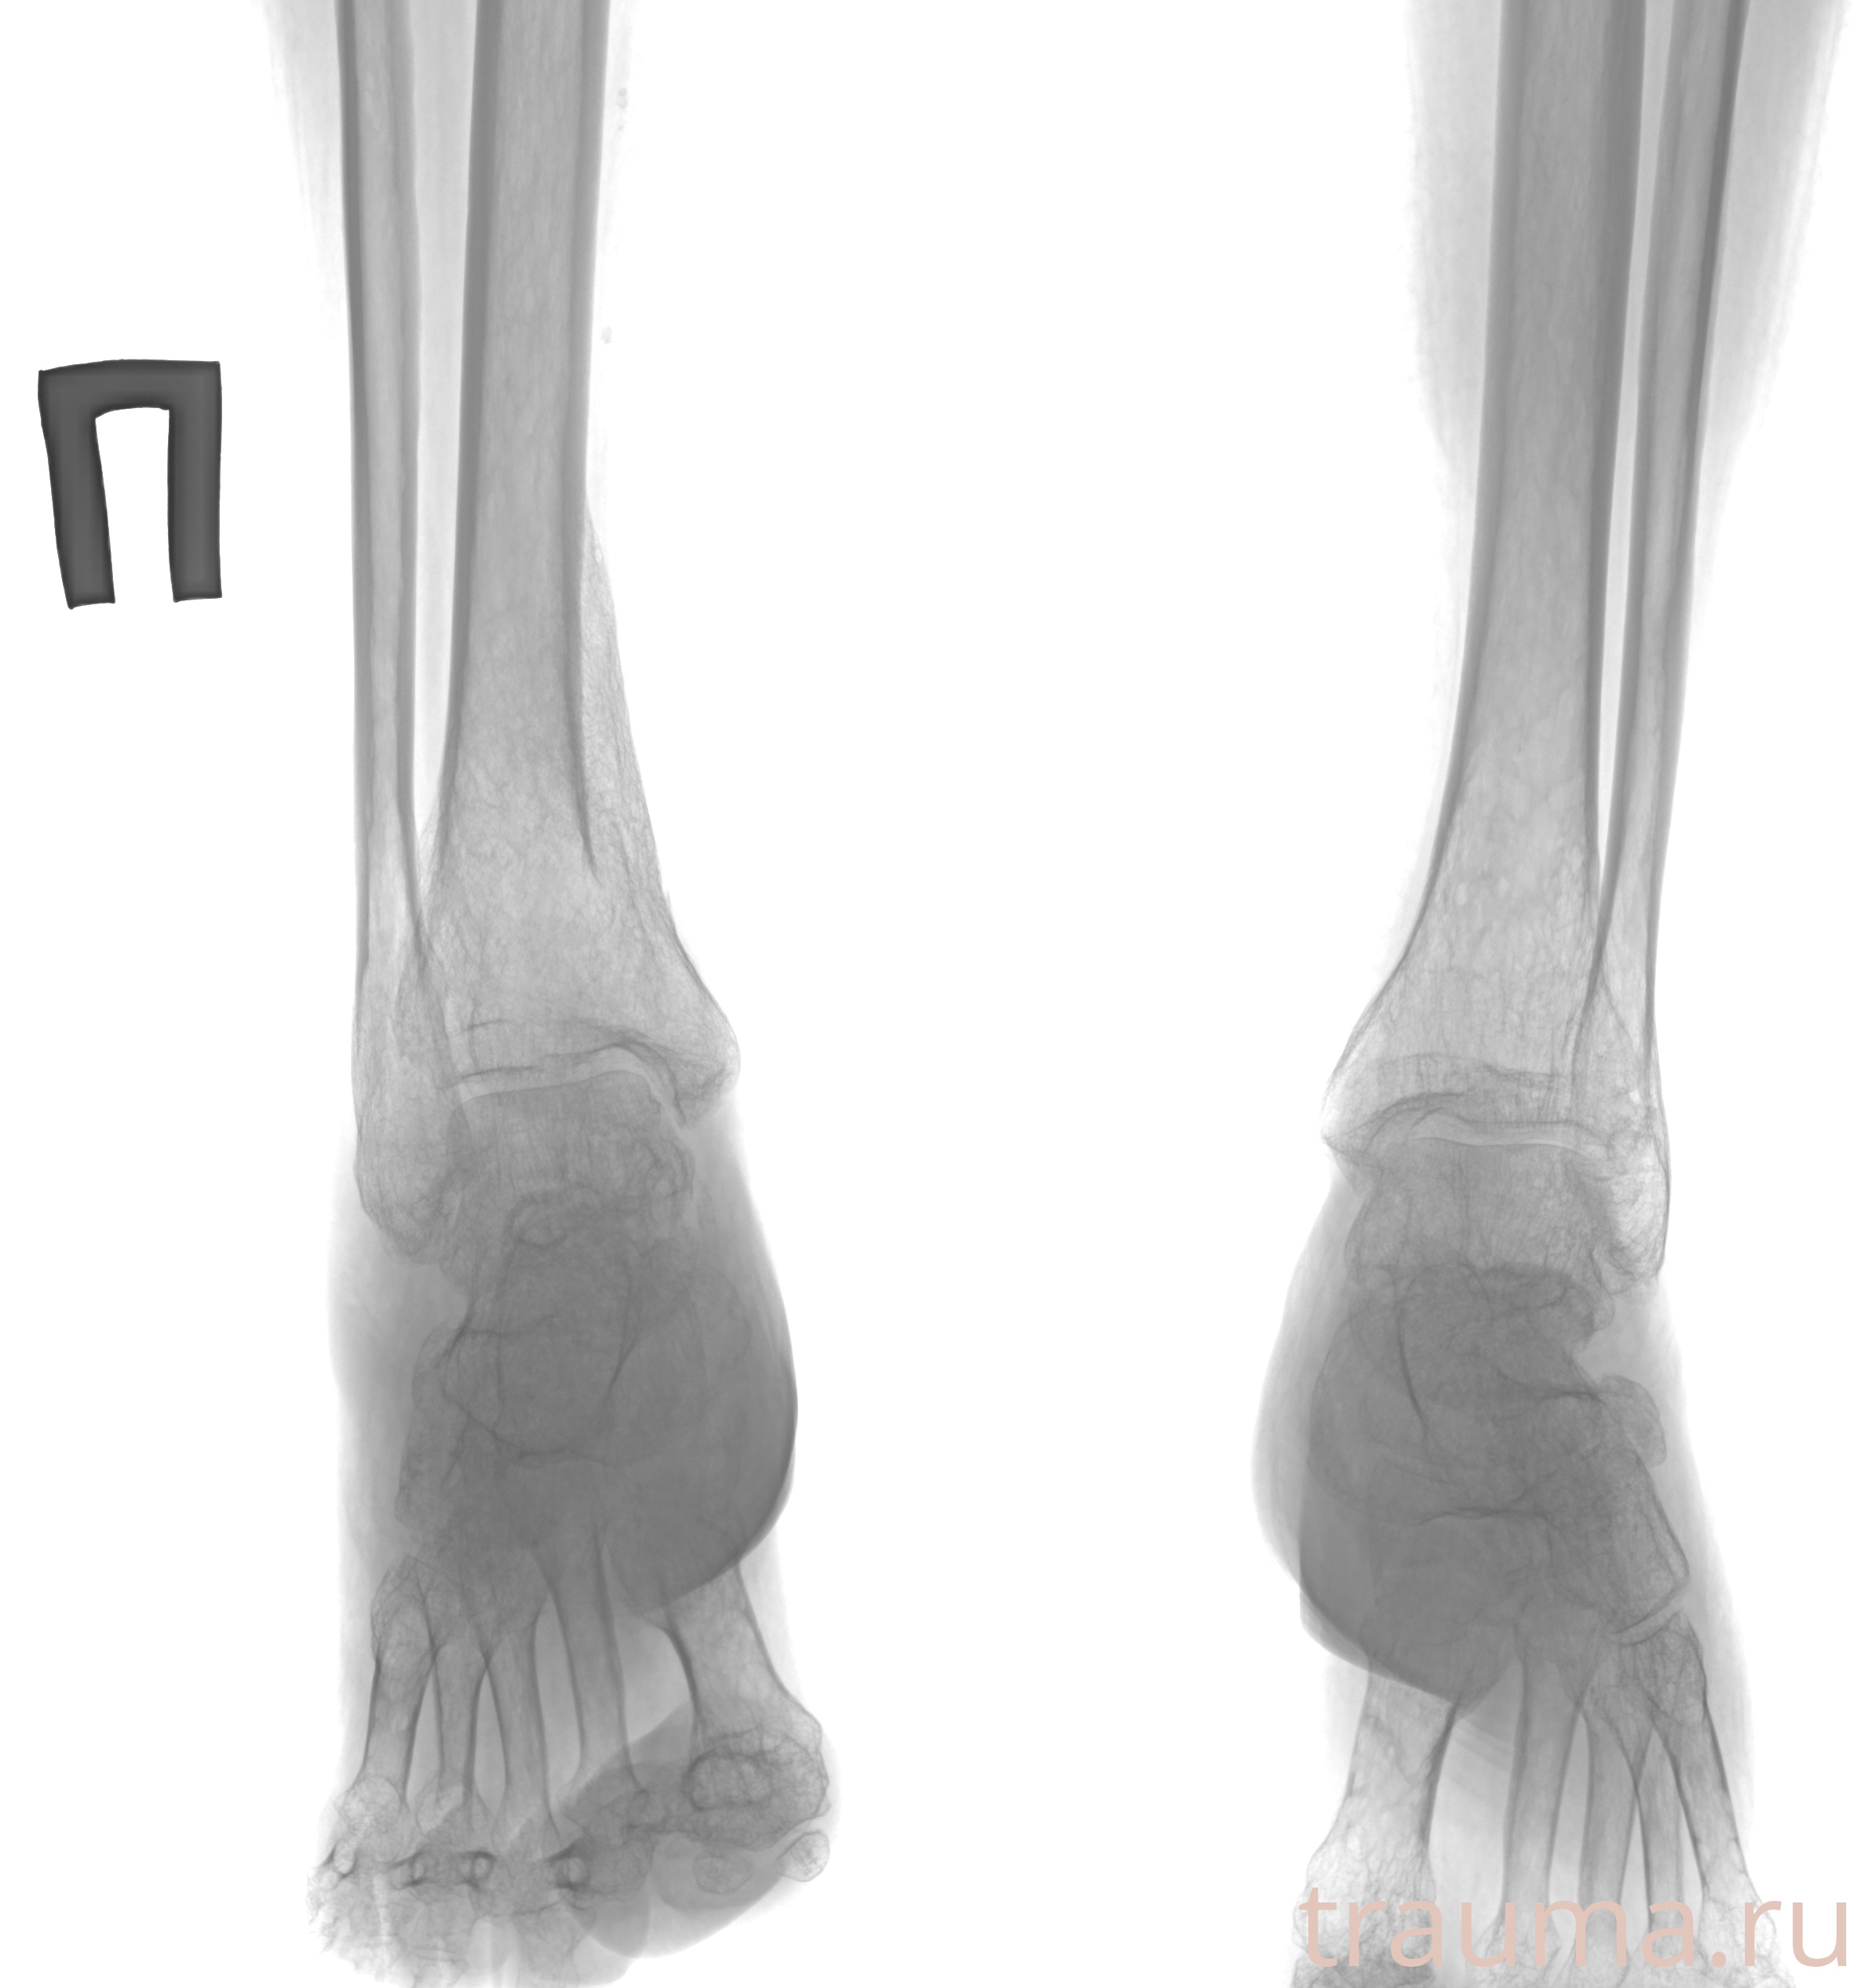

Рентген на дому: по вашему адресу приезжает врач-рентгенолог, травматолог-ортопед с мобильным рентгеновским аппаратом, проводит диагностику травмы или заболевания, делает необходимые рентгенограммы, дает рекомендации по дальнейшему лечению. Получить качественные снимки в домашних условиях возможно благодаря уникальной методике, разработанной МосРентген Центром для института  Склифосовского